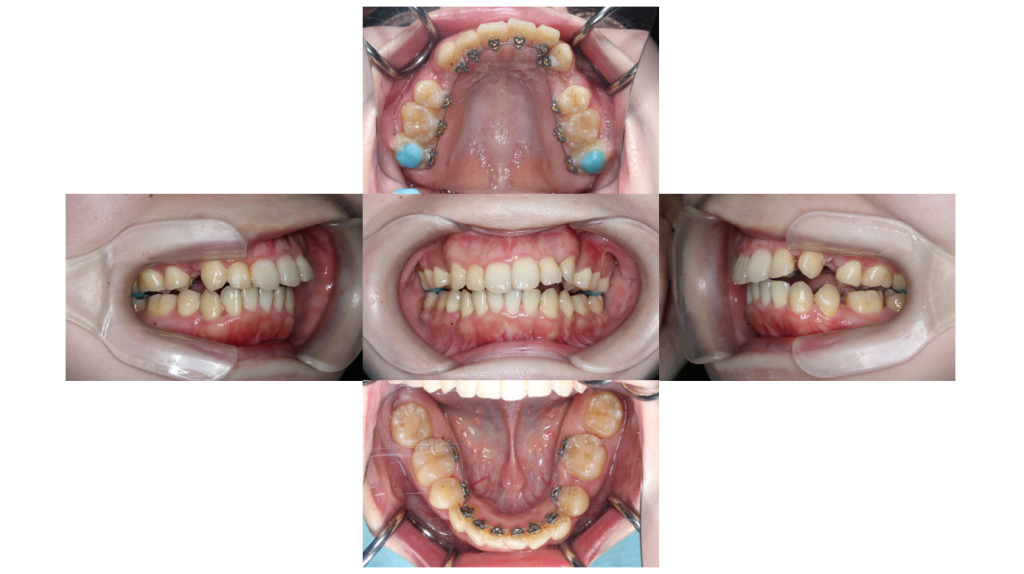

2ヶ月経過

叢生・裏側矯正の症例2ヶ月経過し、内側に入り込んでいた歯も並んできました。

3ヶ月経過

叢生・裏側矯正の症例小さな仮の装置がついていた左上犬歯も動いてきました。